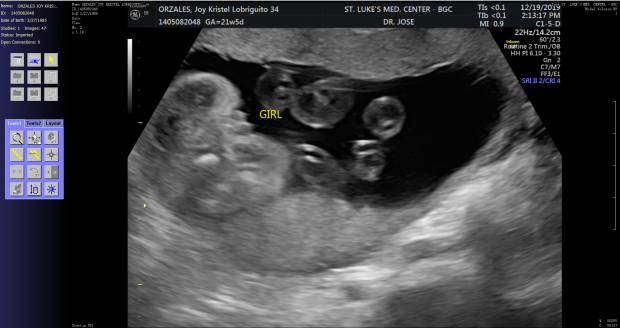

I never wrote something about our incoming baby girl, not because I do not want to but because I want to just keep it to ourselves after what happened to Baby Tres. Baby Aeda will be our rainbow baby.

But I am already 30 weeks pregnant and expecting to delivery this wonderful baby by April 4, 2020. She will be named after her grandmothers, Aida and Cecilia. The IV (pronounced as Ivy) is a constant reminder that she is our fourth child so the kids will never forget that they have an angel sibling who is constantly protecting all of us.

During the congenital scan, the sonologist was not able to get the full view of her one foot because she was holding it during that time.

We were also told that her kidney was a bit dilated that time so we had to have it rechecked on our next ultrasound. So during our reassessment, our sonologist that time explained to us the possibilities why the kidney was dilated. But reassured us that there is nothing to worry now and we just need to have her reassessed after delivery. For now, there is nothing that we can do but wait for the delivery.